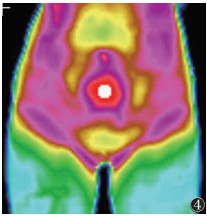

服用温经汤1个疗程后,子宫及宫颈区细胞代谢热明显较前增加,热断层过程中与腹股沟淋巴迅速连成一片;下腹部及腰骶部向上的脊柱可见竖条状细胞代谢热增加,呈上升趋势,热辐射值均明显高于用药前(均P < 0.05)(图 4~6)。

| 图 4 女,22岁,原发性寒湿凝滞型痛经,子宫及宫颈区细胞代谢热明显较前增加 |